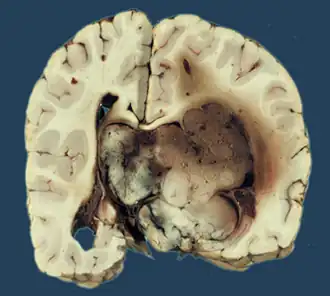

![]() Макропрепарат хориоидпапилломы | |

Макроскопически опухоль представляет собой округлый узел с мелкозернистой или ворсинчатой поверхностью. Иногда при наличии капсулы поверхность новообразования гладкая. На разрезе ткань серо-розовая, мелкозернистая, несколько плотнее ткани здорового мозга. В ряде случаев содержит гладкостенные кисты с серозным, слизеподобным или кальцифицированным содержимым[1].